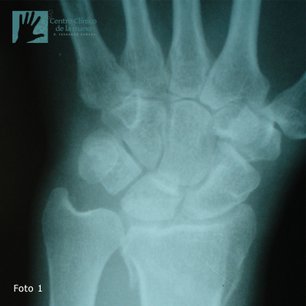

Fractura de Muñeca